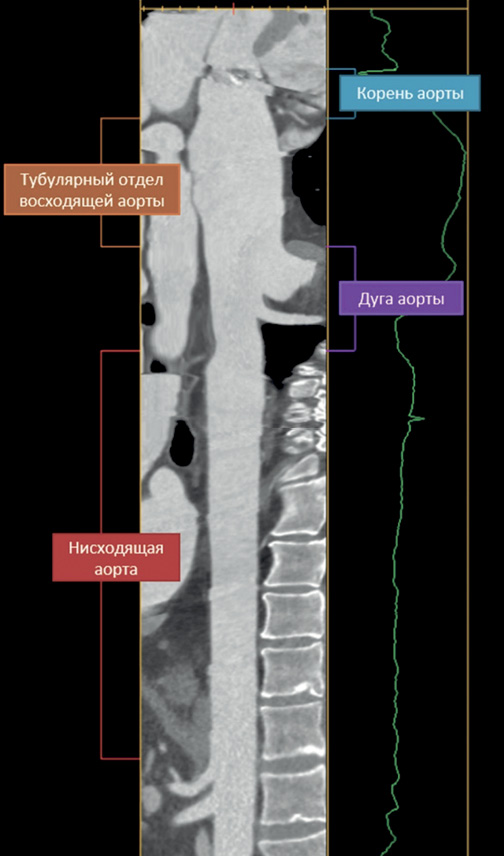

Длину аорты измеряли перпендикулярно центральной линии просвета сосуда в следующих сегментах: (i) от уровня фиброзного кольца аортального клапана до сино-тубулярного соединения (корень аорты); (ii) от сино-тубулярного соединения до уровня БЦС (тубулярная часть восходящей аорты); (iii) от БЦС до истмуса аорты (дуга аорты); (iv) от истмуса аорты до устья чревного ствола (нисходящая аорта) (рис. 1).

Рис. 1. Трек измерения длины сегментов грудной аорты.